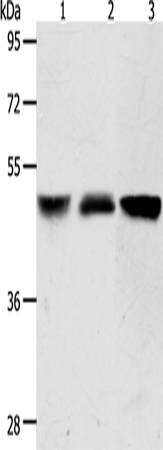

分类: 科研抗体货号: P07791别名: AF10应用: WB反应种属: Human